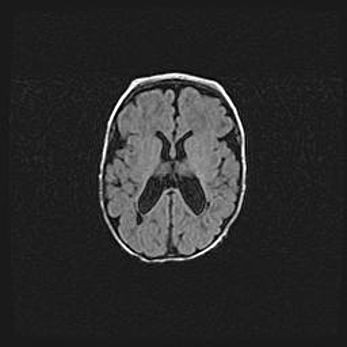

Множественные кисты обоих полушарий головного мозга, наибольшая из них в правой затылочной области. Ассиметричная атрофическая гидроцефалия.

Возраст: 7 месяцев

Вес: 5660 г

Пол: мужской

Окружность головы: 41,5 см

Срок гестации: 28-29 недель

Кисты головного мозга развиваются в результате многоочаговых некрозов вещества мозга и возникают вследствие перенесенной перинатальной инфекции, менингитов, энцефалитов, асфиксии, родовой травмы, расстройств мозгового кровообращения различного генеза. Образованию кист в веществе головного мозга плодов и новорожденных способствуют такие факторы, как высокое содержание в нем воды, недостаточная (или отсутствие) миелинизация и слабая астроглиальная реакция на повреждение.

Кисты могут сочетаться с гидроцефалией и другими поражениями головного мозга.